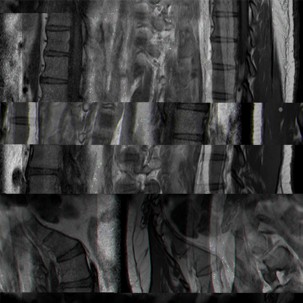

El detonante es una experiencia de dolor lumbar padecida durante casi diez años que no parecía tener una causa más allá de periodos de estrés sostenidos. Después de dos crisis seguidas que provocaron periodos de dolor incapacitante, en los que la movilidad del productor se vio comprometida, se realizaron estudios en los que se incluyó la realización de una resonancia magnética. Con los resultados de esta, un especialista en traumatología diagnosticó dos hernias de disco, una protusión y una extrusión que eran las causantes del dolor.

Antes del diagnóstico el dolor incapacitante era una experiencia cercana a lo real, debido a que la dolencia no correspondía con los síntomas, las sensaciones más intensas no podían ser significadas del todo, y los tratamientos prescritos no daban una solución efectiva. La causa de las lesiones no ha podido ser determinada (parece que eso no es posible ya); sin embargo, el conocer de dónde provienen los episodios de dolor permitió al productor comenzar a negociar con las sensaciones y su posible paliación. Conocer el origen del dolor permitió probar con terapia y el uso de tratamiento que no fue del todo efectivo. Posteriormente, con actividad física implementada en el día a día, ha sido posible lidiar con el dolor, si no eliminarlo, gracias a la simbolización, a darle una explicación que proviene directamente de la imagen provista por una técnica de representación visual.

La propuesta de metodología consiste en el trabajo y manipulación de las imágenes generadas mediante resonancia magnética y la representación gráfica de diferentes signos vitales y procesos de actividad física registrados durante siete meses, a partir de un reloj electrónico colocado permanentemente en la muñeca del productor y que proporciona información relacionada con el ritmo cardiaco, los ciclos del sueño, la calidad de la actividad física, entre otros, todo lo cual es representado de forma gráfica.

Una vez obtenidas ambas imágenes, fueron manipula- das a través de software de edición de mapa de bits, y posteriormente procesadas mediante la técnica de data bending o alteración de bits. Este es un proceso de manipulación de archivos digitales que tienen un formato nativo y que son reproducidos y modificados a tra- vés de otro software diseñado para formatos diferentes.

Un ejemplo de esto sería manipular un archivo de imagen a través de un software de edición de audio. Para lograrlo, es necesario convertir la información digital en bits, y después, por medio de un software de edición de audio, manipular el archivo a través de efectos y procesos sonoros, para después reconstruir los archivos resultantes en imágenes (Betancourt, 2014, p. 18).

Esta segunda etapa de manipulación de archivos se desarrolla en un estado cercano a lo real, pero desde un punto de partida simbólico, en el que se sabe qué tipo de información se está manipulando, pero no se tiene ninguna certeza o parámetro de aquello que resultará. Las imágenes presentadas son producto del automatón, concepto propuesto por Aristóteles en el segundo libro de la Física (Aristóteles, s.f./2015), y que se establece como una forma de azar en la que es posible tener un parámetro de cuáles pueden ser los resultados posibles: un cierto nivel de predictibilidad de lo aleatorio, una forma de azar en el que se tiene un somero control de aquello que resultará de un proceso azaroso.